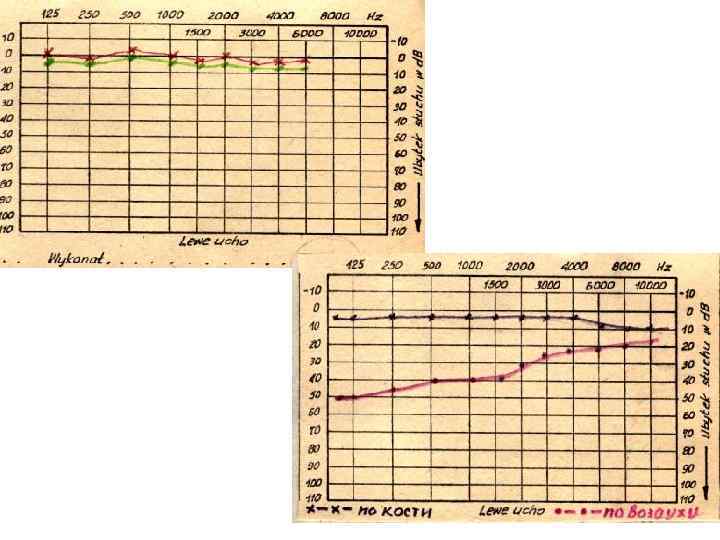

ЗВУКОВОЙ (слуховой) АНАЛИЗАТОР üЗвукопроведение (кондукция) - костное - воздушное üЗвуковосприятие (перцепция)

Клинические формы хронического гнойного воспаления среднего уха q Мезотимпанит q Эпитимпанит q Мезоэпитимпанит

Мезотимпанит

Мезотимпанит

Эпитимпанит

Эпитимпанит